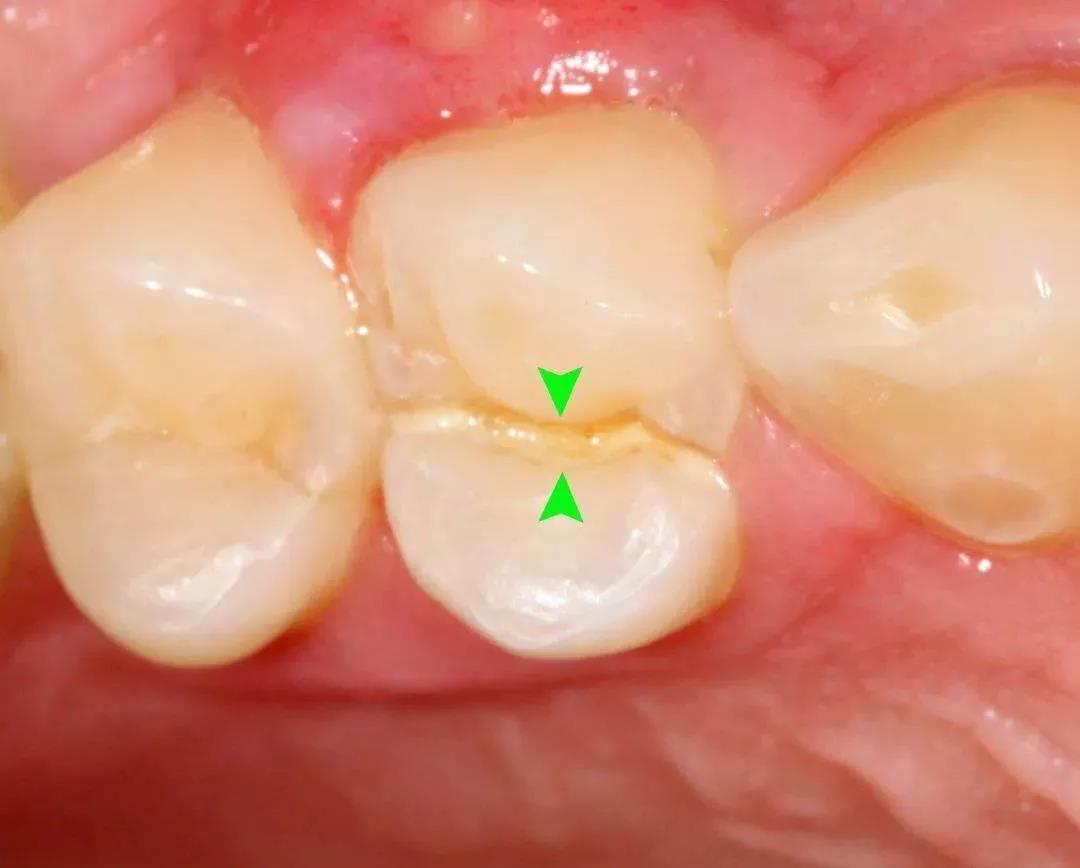

牙隐裂又称“不全牙裂”或“牙微裂”,是指牙冠表面出现非生理性的细小裂纹。

这种细小的裂纹常会深入到牙本质结构,是牙齿敏感以及牙痛的原因之一。

☛ 裂纹较浅:肉眼很难看到裂纹,偶尔吃过冷或过热的食物时,牙齿会产生短促又剧烈的疼痛。

☛ 裂纹较深:牙齿会经常性地疼痛,咬合不适或有轻度的叩痛感。

☛ 裂纹深达牙本质:牙齿会出现慢性牙髓炎症状,冷热刺激患牙时,产生剧痛,咀嚼过程中可能会疼痛难忍。